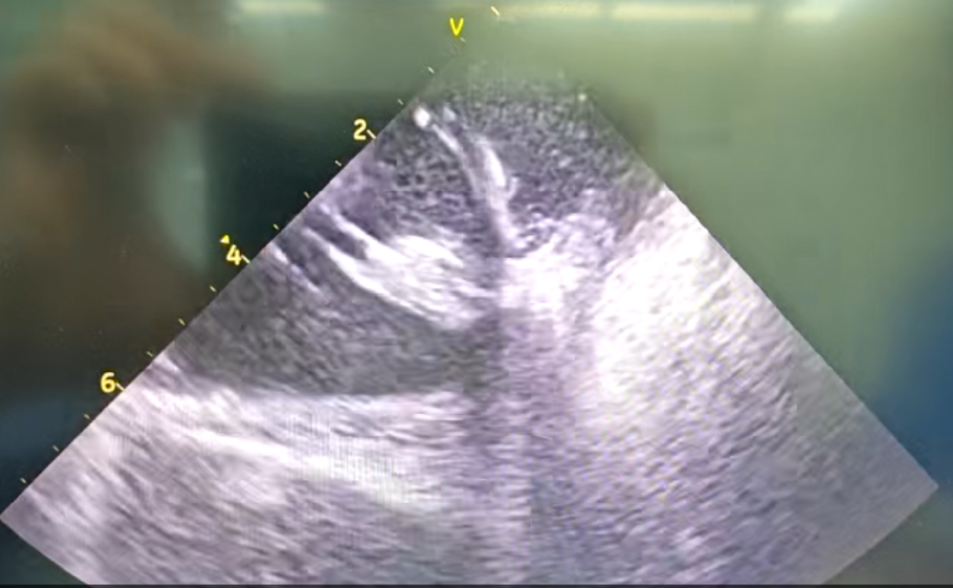

部分内膜室速靶点电位

王林林主任医师谨慎操作,成功进入心外膜达到病变位置。术中,患者反复自发多形态室速,且转为室扑,同时出现血流动力学不稳定,需多次电除颤方能终止发作,标测难度极大。这就要求医疗团队必须在有限的标测时间内精准定位室速消融靶点,并结合心内外膜基质特征制定消融策略。经针对性消融后,患者未再自发室速,且室性早搏转为单一形态,经判定为右心室乳头肌来源,随即予以一并消融。术后经心室程序电刺激验证,室速未再被诱发。